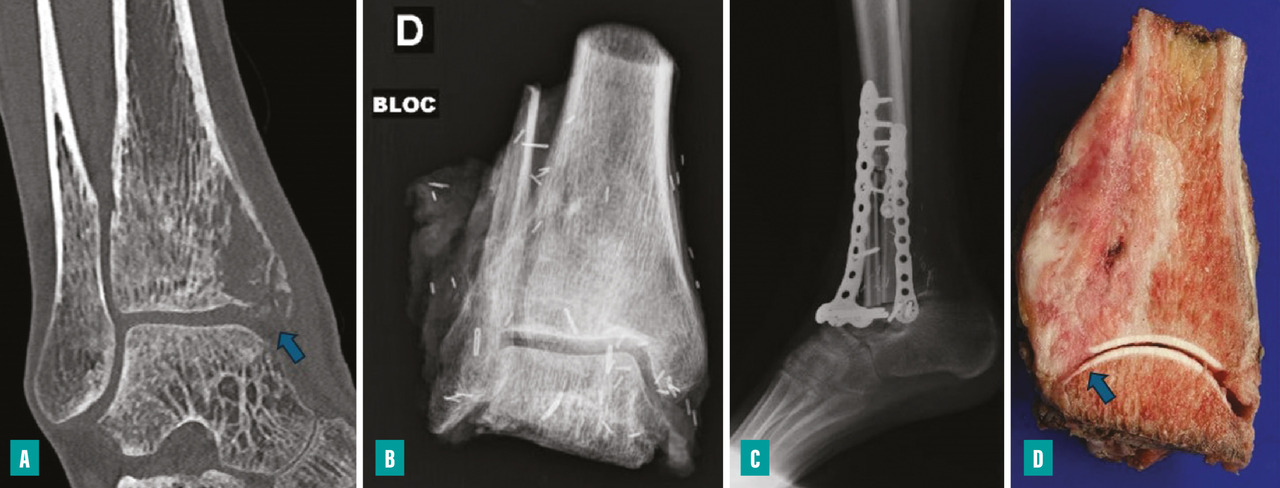

Pour les sarcomes des membres, la préservation de la fonction articulaire est le facteur déterminant. Dans la mesure du possible, les chirurgies avec préservation épiphysaire doivent être privilégiées (fig. 1). En cas d’atteinte épiphysaire, le choix de la technique opératoire dépend de la présence ou non d’un envahissement intra-articulaire, qui nécessite alors de recourir à une résection dite «  extra-articulaire  », techniquement plus exigeante (fig. 2). L’imagerie par résonance magnétique (IRM) a une place de choix pour identifier cette contamination articulaire.